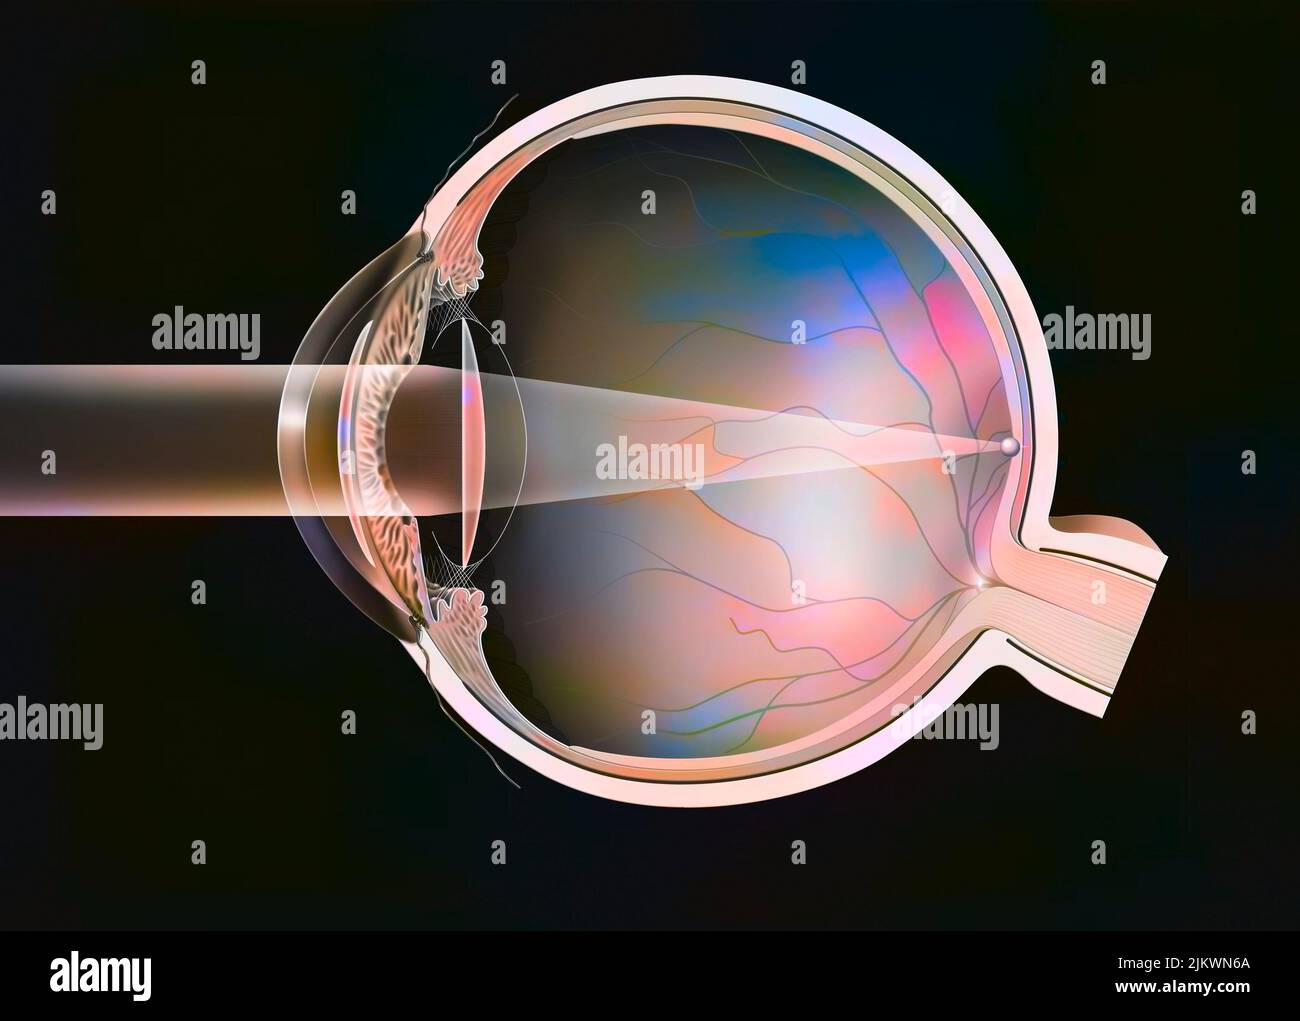

RF2JKWT9A–Oeil, cataracte, phacoémulsification - étape 2: Consiste à casser la lentille avec une sonde.